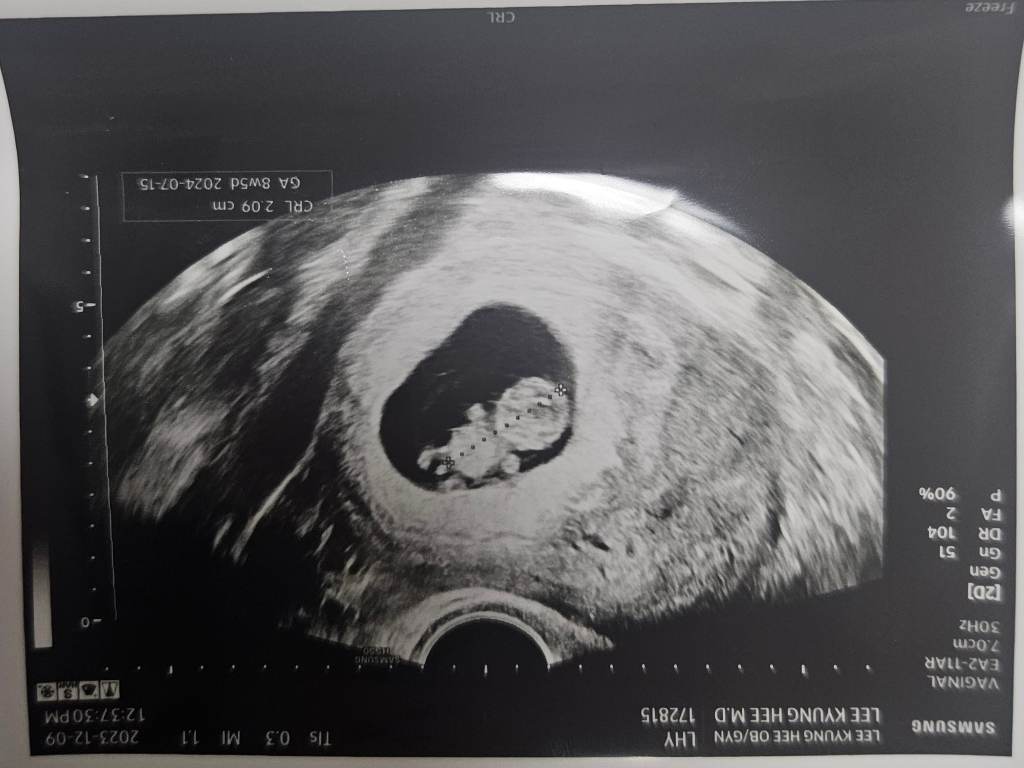

임신9주차인데 아들같다는데 성별을 벌써 알수가 있나요?

9주차인데 아들같다네요 다리사이 저게

혈관이 안보여서 탯줄은 아닌 거 같다고..

벌써 성별을 알 수 있나요?

제가 알기로늘 15주는 되야 안다고 들어서요

일반적으로 15주 되어야 성별확인이 가능하다고 하긴 합니다.. 9주는 좀 빠른건 맞지만.. 개인차가 있으니까 조금 잘 보일수도 있고, 아마 확실한건 아닌거 같네요

임신 9주가 되면 태아의 생식기 발달이 시작되며, 호르몬 변화에 의해 남자와 여자로 구분됩니다. 여아의 생식기 발달은 임신 11주까지, 남아의 경우에는 임신 13~14주 경에 완료됩니다. 이 시기부터 초음파를 통해 성별을 확인할 수 있지만, 임신 20주 이후에는 더 명확하게 남자와 여자를 구별할 수 있습니다.

태아의 다리 사이에 나타나는 구조물이 남아인지 여아인지를 판단하는 데, 그것만으로 충분하지 않습니다. 여아의 경우 외음부가 두 개 또는 네 개의 선으로 관찰되어야 하며, 남아의 경우 음경이 위 앞쪽으로 향하고 음핵이 아래쪽에 위치하는 것으로 확인됩니다.

때로는 임신 12~16주에 수행한 초음파 검사에서, 태아의 음경이 위 앞쪽을 향하게 나타날 수 있습니다. 이런 경우를 일반적으로 '각도법'이라고 알고 있으며, 이로 인해 남아로 잘못 판단되기도 합니다. 따라서 임신 20주에 실시되는 정밀 초음파를 통해 성별을 확실하게 확인하는 것이 더 정확하며, 혼란을 줄일 수 있습니다.

아시듯 15주차가 되어야 명확히 보이지만 지금처럼 초음파에 성기가 잘 보이니까 아들일 가능성이 매우 높아보입니다.